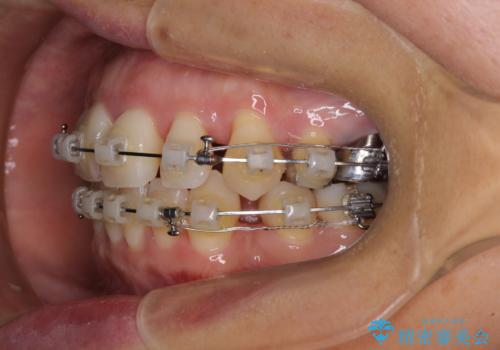

- クリアブラケット

- 2年2ヶ月

半年もしないうちに八重歯は解消し、治療も当初予定通り2年強で終えることができました。